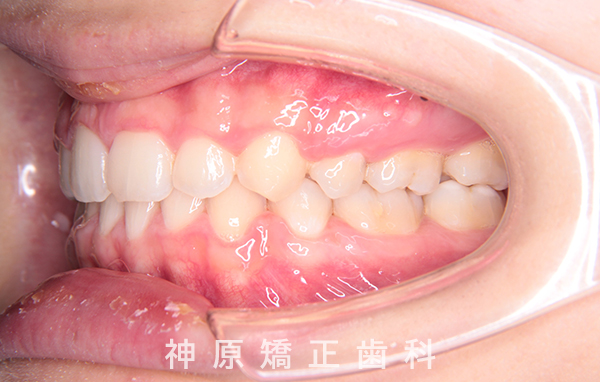

上下顎前突症例(口ゴボ)

Upper And Lower jaw Protrusion Cases

17歳 女性

初診時

マルチブラケット装着1年後

治療終了

口元の突出感を改善するために小臼歯の抜歯が必要と判断しました。抜歯スペースを活用し、前歯を可能な限り後方へ移動させるため、上下に矯正用アンカースクリューを使用する計画です。患者様とご家族に十分な説明を行い、治療ゴールに同意を得た上で矯正治療を開始しました。矯正治療の結果、側貌はE-lineに調和したバランスの良い仕上がりとなりました。